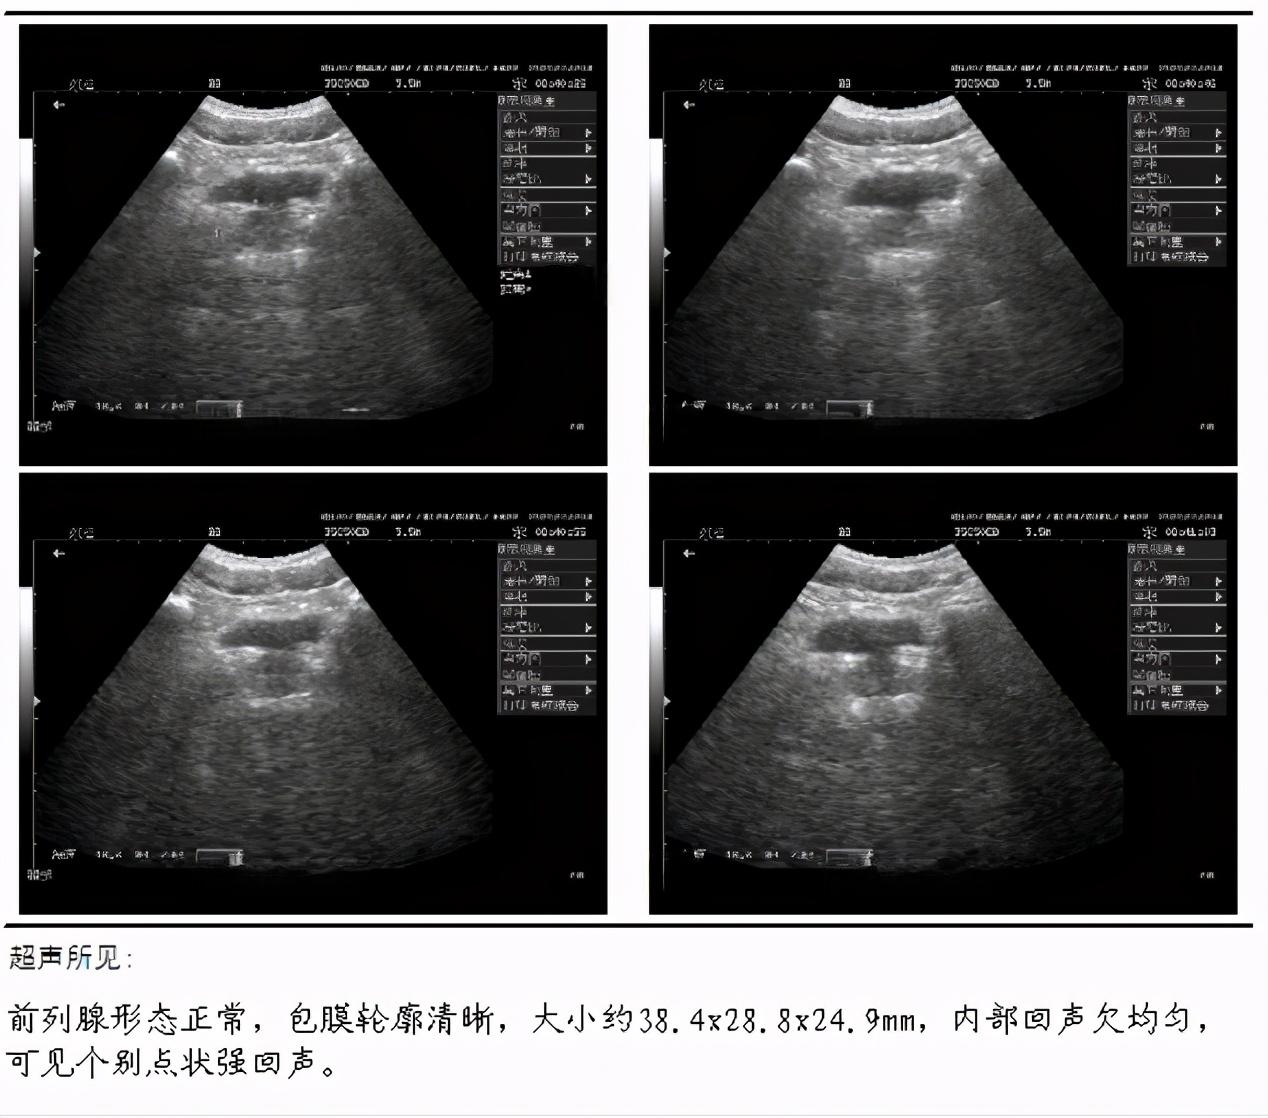

Image